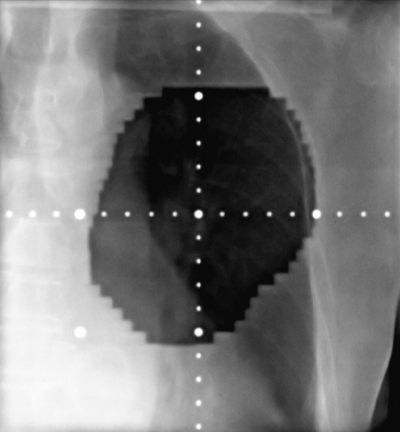

体温 36.4 ℃。脈拍 68/分、整。血圧 122/72 mmHg。呼吸数 18/分。SpO2 97 %(room air)。呼吸音に異常を認めない。血液所見:Hb 10.8 g/dL、白血球 5,400。CRP 0.9 mg/dL。肺癌治療前と今回来院時の胸部エックス線写真及び放射線治療の照射野を示す。

治療前